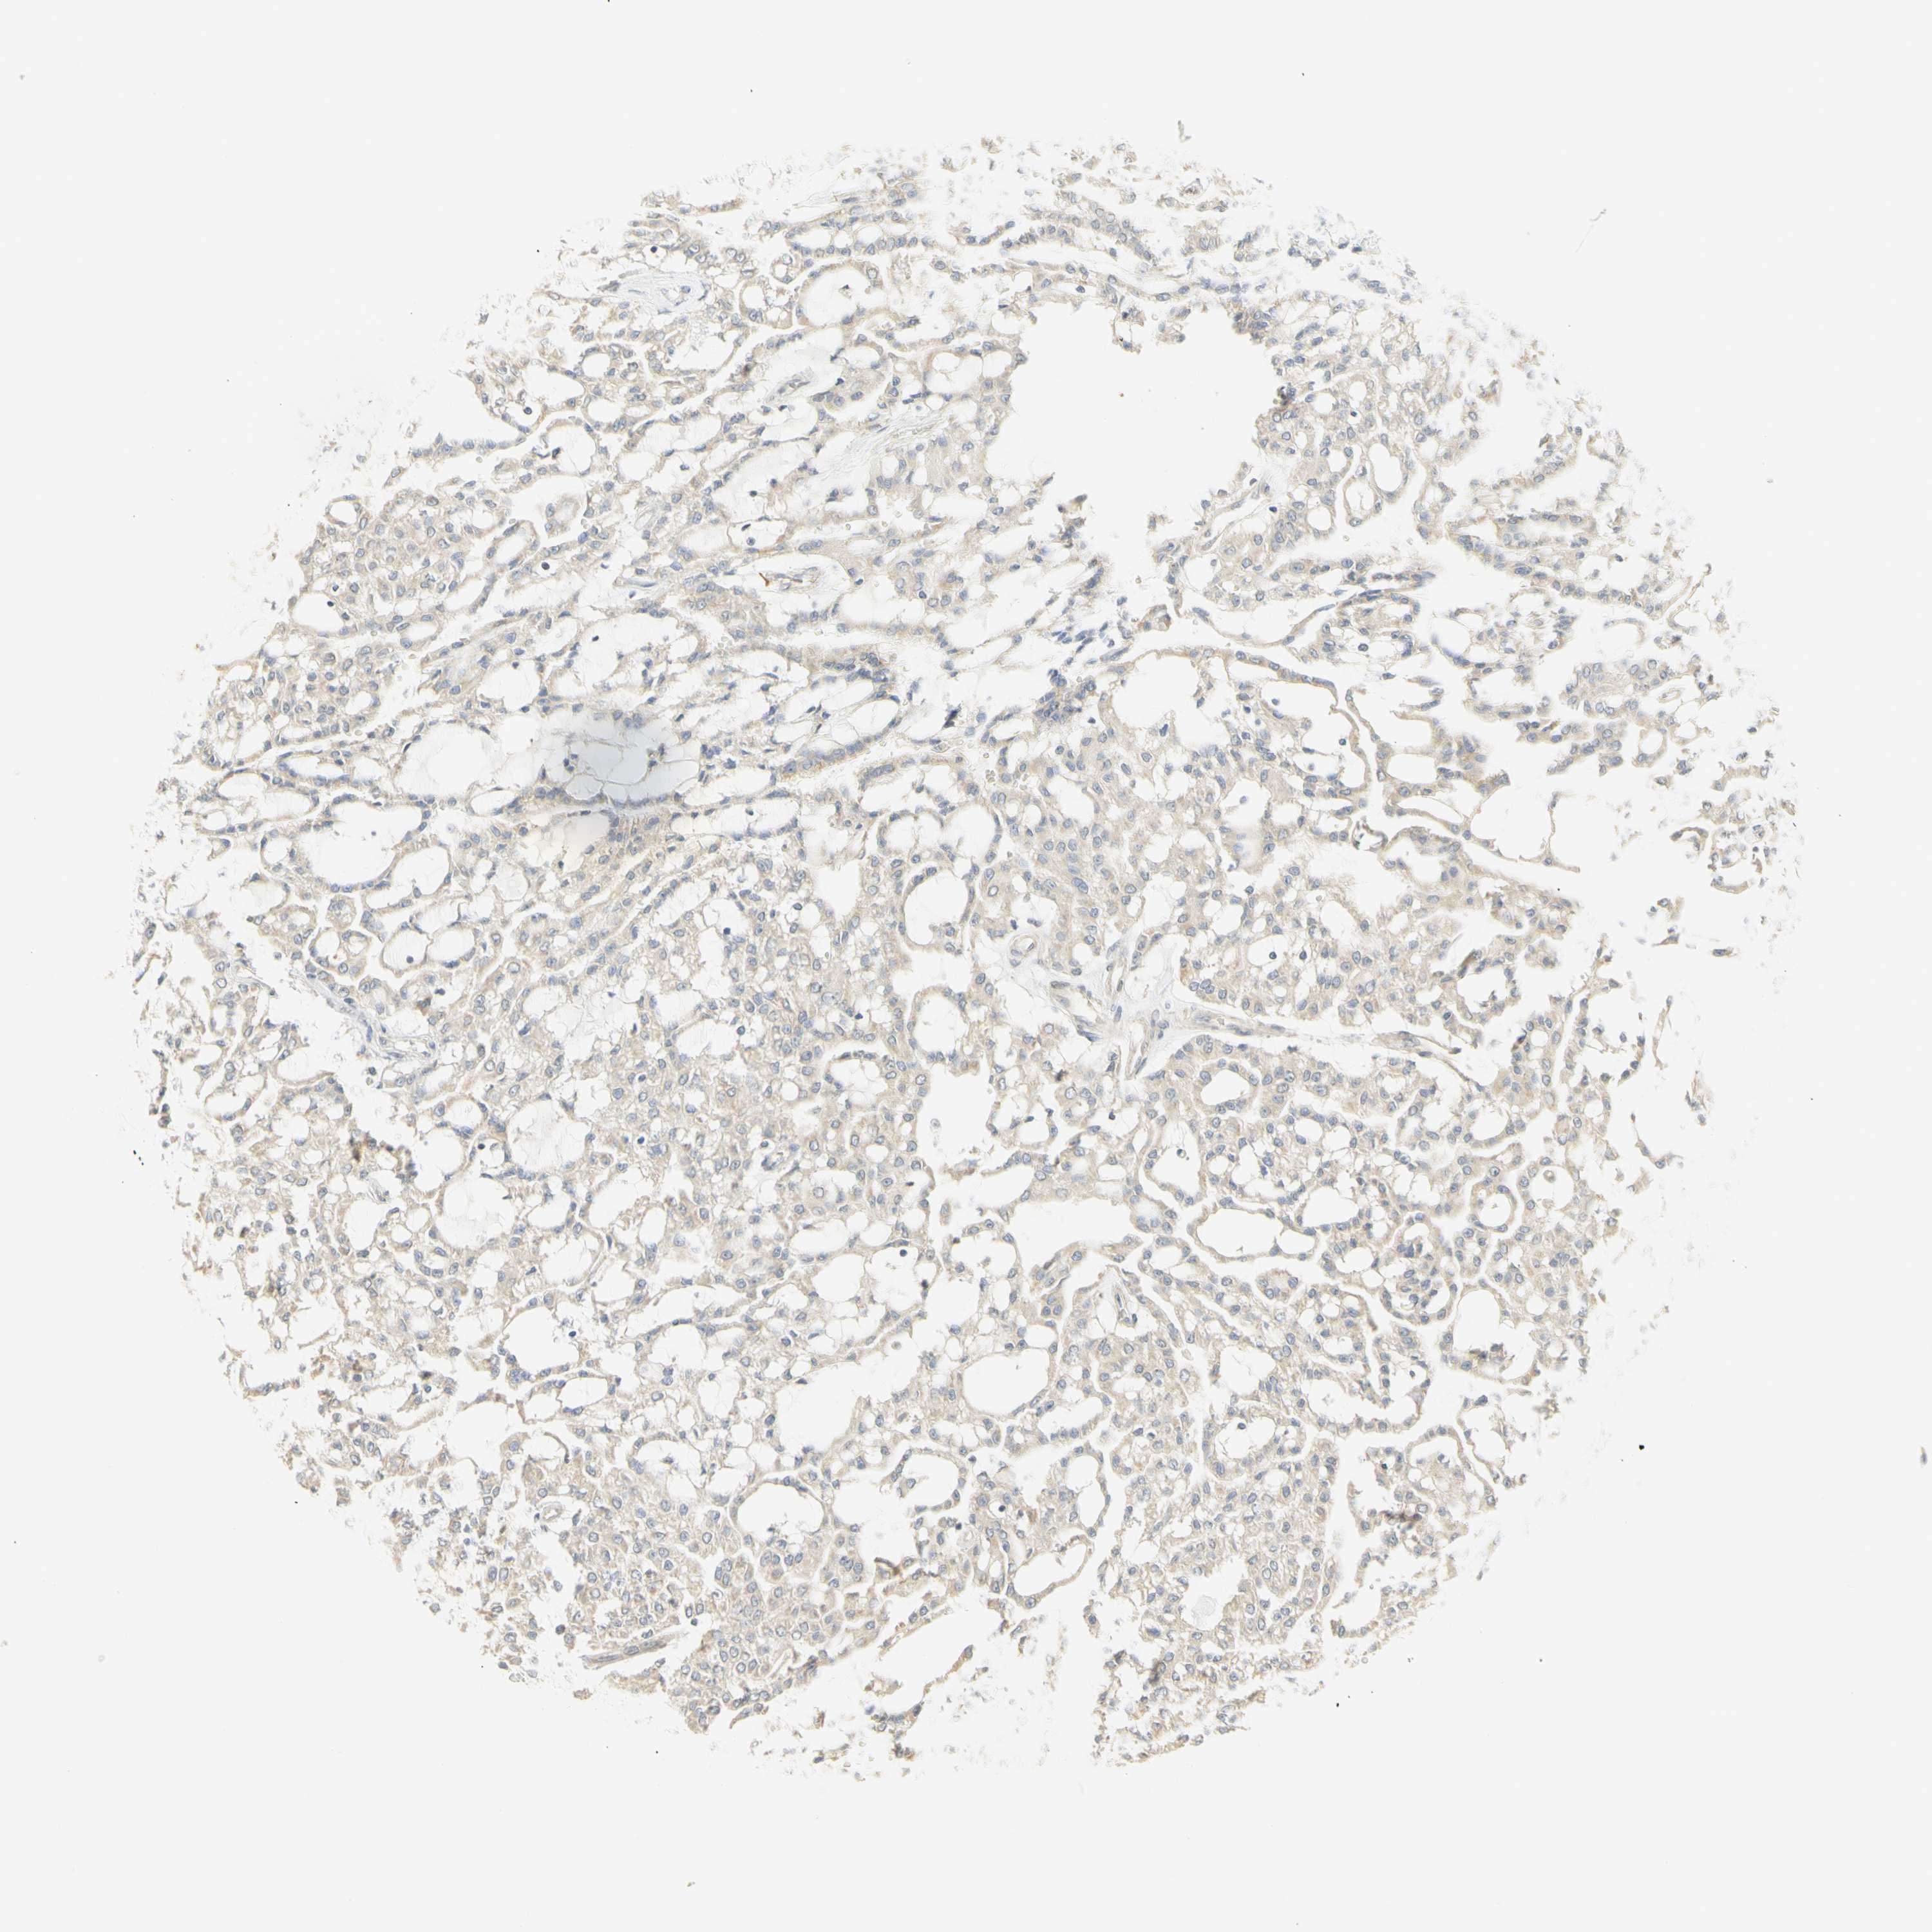

KIDNEY RENAL CLEAR CELL CARCINOMA (VALIDATION) - Interactive survival scatter ploti

The Survival Scatter plot shows the clinical status (i.e. dead or alive) for all individuals in the patient cohort, based on the same data that underlies the corresponding Kaplan-Meier plots. Patients that are alive at last time for follow-up are shown in blue and patients who have died during the study are shown in red.

The x-axis shows the expression levels (FPKM) of the investigated gene in the tumor tissue at the time of diagnosis. The y-axis shows the follow-up time after diagnosis (years). Both axes are complimented with kernel density curves demonstrating the data density over the axes. The top density plot shows the expression levels (FPKM) distribution among dead (red) and alive patients (blue). The right density plot shows the data density of the survived years of dead patients with high and low expression levels respectively, stratified using the cutoff indicated by the vertical dashed line through the Survival Scatter plot. This cutoff is automatically defined based on the FPKM cutoff that minimizes the p-score. The cutoff can be changed by dragging the vertical line or by entering a cutoff value in the square labeled "Current cut-off".

Under the Survival Scatter plot the p-score landscape (black curve; left axis) is shown together with dead median separation (red curve; right axis). Dead median separation is the difference in median mRNA expression between patients who have died with high and low expression, respectively. It is calculated as follows: median FPKM expression of dead patients with high expression - median FPKM expression of dead patients with low expression. This is intended to aid the user in visually exploring custom cutoffs and the associated p-scores and dead median separation.

Individual patient data is displayed and can be filtered by clicking on one or more of the category buttons on the top of the page. Categories describing expression level and patient information include: high, low, alive, dead, female, male and tumor stages. The scale of the x-axis can be toggled between linear and log-scale by clicking on the "x log" button. Mouse-over function shows TCGA ID, patient information and mRNA expression (FPKM) for each patient.

& Survival analysisi

Kaplan-Meier plots summarize results from analysis of correlation between mRNA expression level and patient survival. Patients were divided based on level of expression into one of the two groups "low" (under cut off) or "high" (over cut off). X-axis shows time for survival (years) and y-axis shows the probability of survival, where 1.0 corresponds to 100 percent.

KIF11 is validated prognostic, high expression is unfavorable in Kidney Renal Clear Cell Carcinoma (validation)

: 3.29

Average pTPM 3.7

Number of samples 100